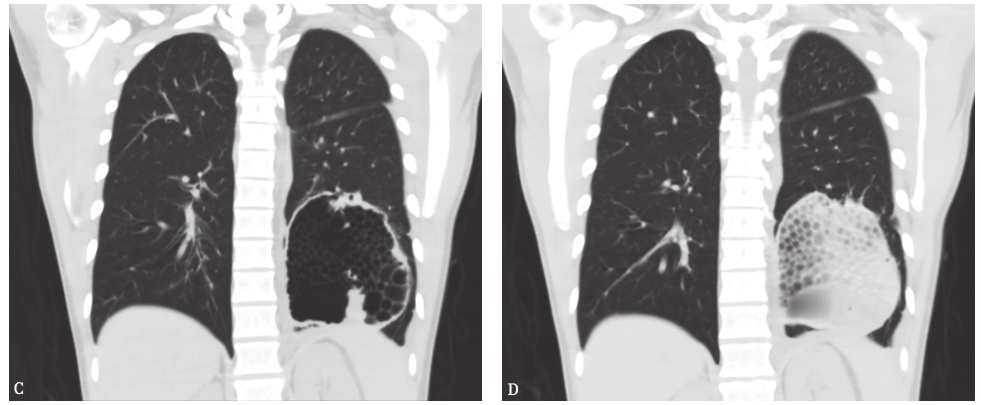

经与胸外科专家会诊讨论、患者本人和家属同意,对患者成功实施了左下叶肺切除术。术后对病灶解剖,进一步证实左下叶各段和亚段支气管通畅,气道无阻塞性病变,但病变张力大,呈球状,经穿刺排气后,剖开病灶,见其内填充大量脓性坏死组织。病理检查见大量干酪样坏死性肉芽肿结节(图14),脓液涂片抗酸染色发现大量抗酸杆菌(图15)。脓液培养发现阳性菌落,经鉴定为结核分枝杆菌,未发现包括厌氧菌在内的其他细菌培养阳性。

图14 病理检查见大量干酪样坏死性肉芽肿结节

A.HE染色,100×;B.HE染色,200×

图15 脓液涂片抗酸染色可见抗酸杆菌(抗酸染色,1000×)

最后诊断:左下肺结核性肺脓肿。